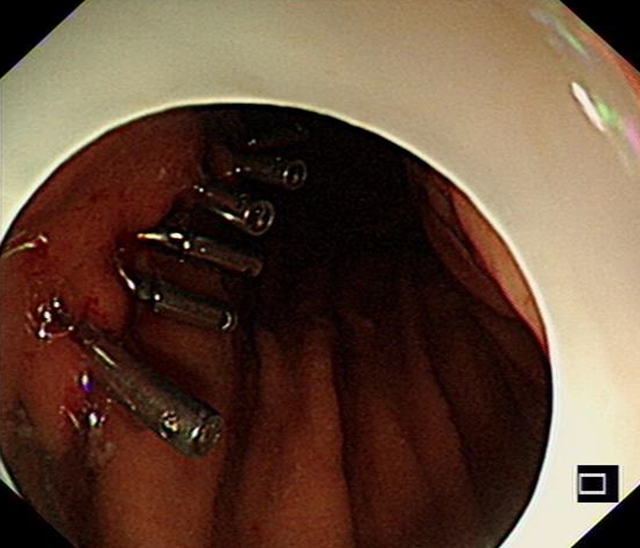

胃内大型黏膜下肿物破溃出现,箭头处为溃疡处

今年春节前夕,72岁的李婆婆被送入西南医科大学附属医院急诊科就诊时,呈休克状态,伴有呕血、黑便与贫血等症状。胃镜检查发现,她是因胃黏膜下肿物破溃出血才导致出现系列症状。

“切掉肿物,出血就会停止。”西南医科大学附属医院消化内科副主任汤小伟副教授介绍,李婆婆体内胃肿物直径约4厘米,邻近肝脏、胰腺等重要脏器。这类肿物常隐藏于黏膜之下,早期没有明显症状,倘若未能及时发现,就会悄悄增大导致疼痛、出血、梗阻,甚至危及生命。